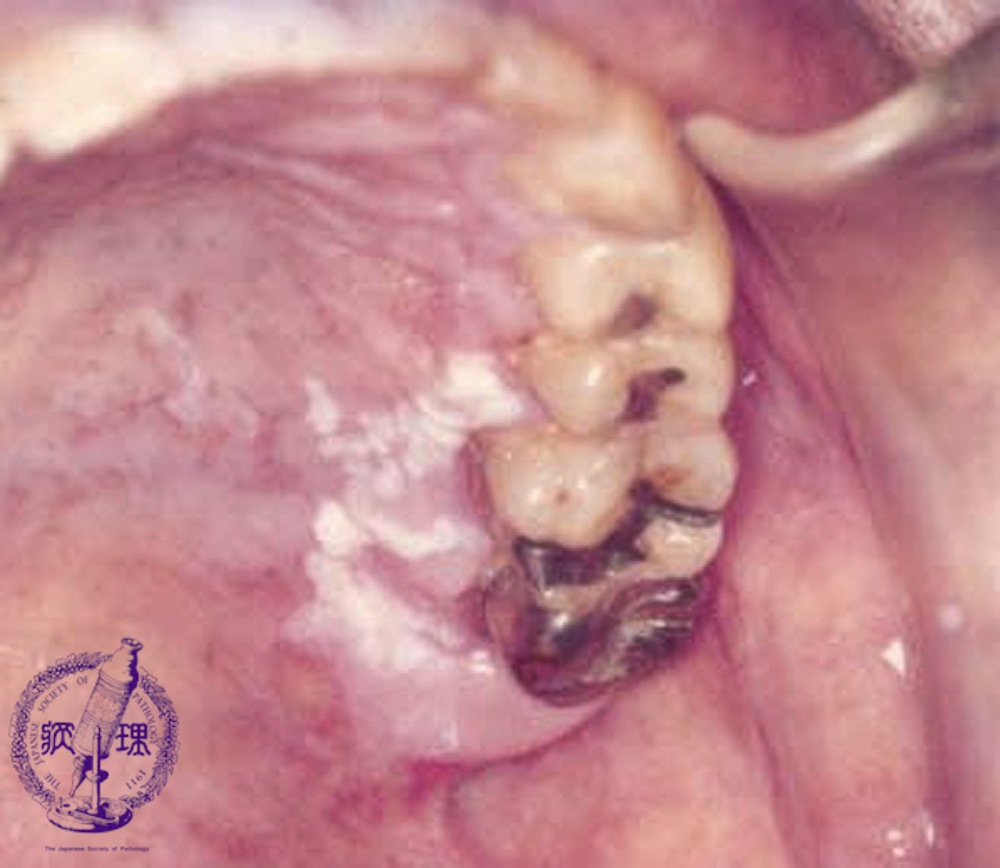

Macroscopic finding:Intraoral photograph. A roughly textured, white lesion spans from the palatal gingiva to the palatal mucosa.